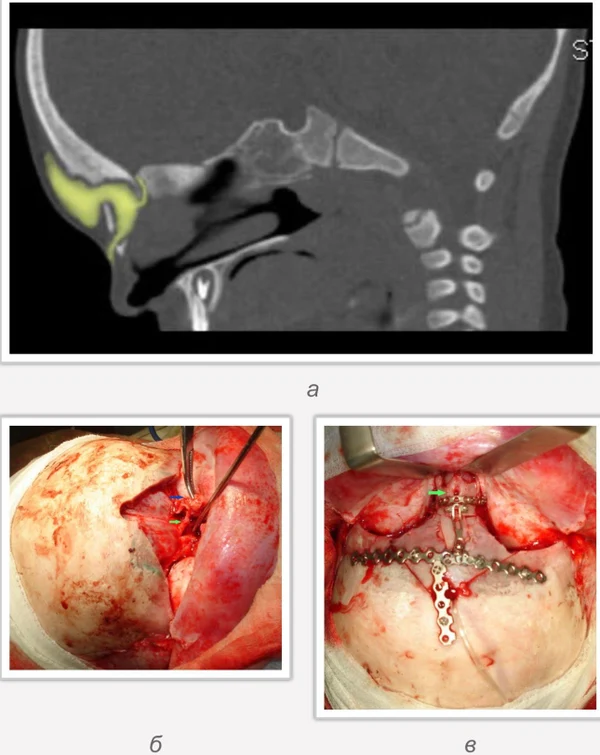

Дермальные синусы, дермоидные кисты и перикраниальные синусы

Иссечение дермальных синусов, дермоидных кист и перикраниальных синусовРазличают краниальный и спинальный дермальный синусы. Дермальный синус может заканчиваться как в мягких тканях, так и проникать в полость черепа или позвоночного канала. В последних случаях имеется высокий риск развития менингита. Лечение только хирургическое, проводится полное иссечение синуса. При распространении синуса до твердой мозговой оболочки свищ иссекается вместе с окружающим участком твердой мозговой оболочки. Дефект твердой мозговой оболочки герметично ушивается.